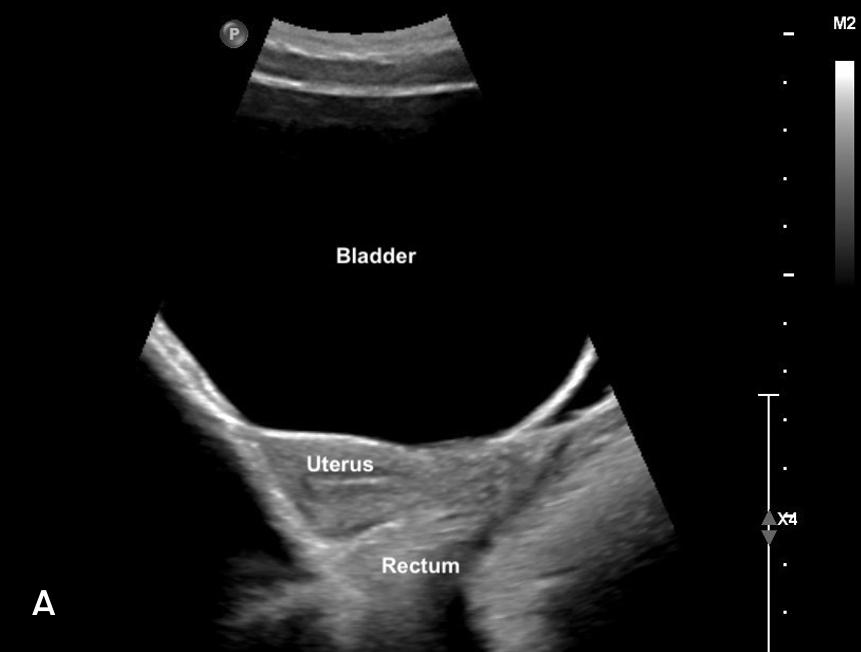

– Sits lower in the pelvis, appearing caudal to the uterus (figure 8)

– Anterior to the rectum (figure 8)

Figure 8: Sagittal view of bladder sonoanatomy in a female patient with a near empty bladder.